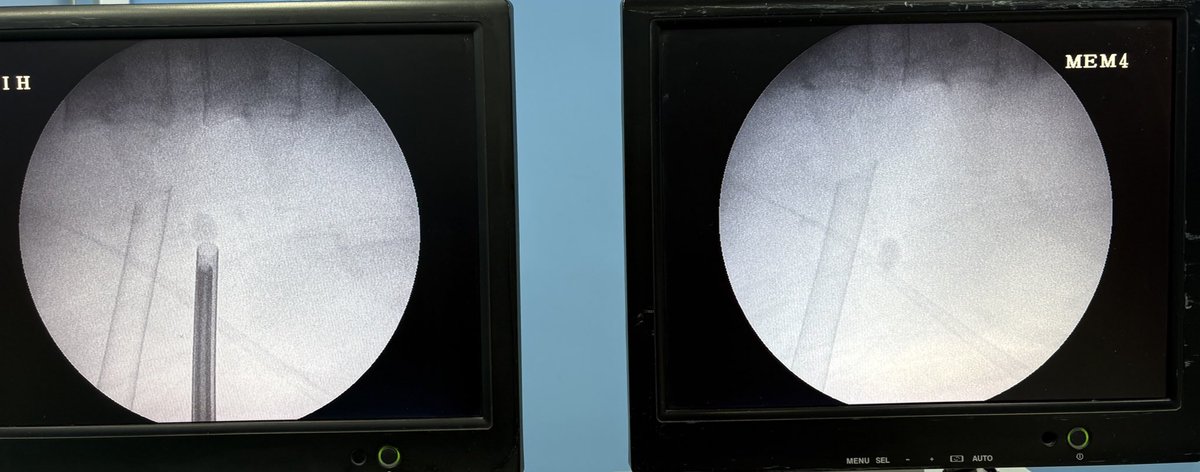

Supine Monoplaner puncture. @UroResidency @docmeetings @Uroweb @so_uro @SIU_urology @CheatUrology @Endo_Society @Talking_Urology @usioffice @urotoday @optionurol @docdilipmishra @DrParimalGharia @sbinhamrii @dr_avreen @Mohamedendourol